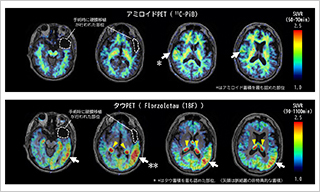

Association of rare APOE missense variants with Alzheimer's disease in the Japanese population